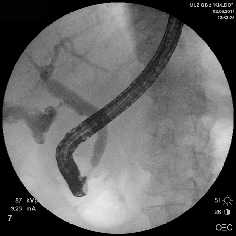

Рубцовая стриктура средней трети холедоха, холедохолитиаз

Полный блок средней трети холедоха (клипса на холедохе)

Несостоятельность культи пузырного протока

Рис. 1. Рентген-фото выявленной патологии

Rg-фото. Бужирование стриктуры холедоха

Rg-фото. Баллонная дилятация стриктуры холедоха

Rg-фото. Стентирование холедоха

Рис. 2. Наиболее часто выполняемые эндоскопические вмешательства